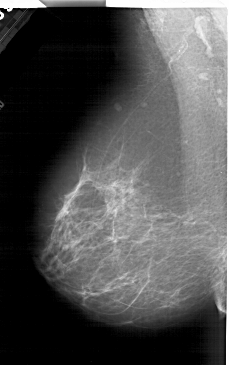

A_2001_1.RIGHT_CC